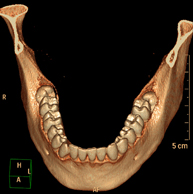

Prueba radiológica que consiste en obtener imágenes del oído de alta definición anatómica (conducto auditivo interno y externo, tímpano, huesecillos del oído), mediante el empleo de un equipo de TC (Tomografía Computarizada). Indicaciones: trastornos de la audición, cuadros vertiginosos, mareos, acúfenos (pitidos). - TC Dental

Prueba radiológica que consiste en obtener imágenes de los huesos maxilares de alta definición anatómica (piezas dentarias, trayecto del nervio dentario), mediante el empleo de un equipo de TC (Tomografía Computarizada). Indicaciones: estudio previo a la extracción dental, estudio previo a implantes, tumores, absceso. - TC Senos paranasales